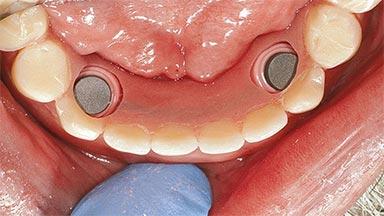

An 83-year-old man presented together with his caregiver at the dental department of the Medical University of Innsbruck, Austria with complaints of swelling in the right maxillary canine area and loss of retention of his 5-years-old mandibular denture. The patient had a significant medical history (20 years) of bipolar affective disorder with moderate depression (F 31.3) and dementia in Alzheimer’s disease (F 00.2). The patient had been in ambulant psychiatric therapy for his depressive illness for the past 20 years. He lived alone and had no children; his sister assisted with daily living. She reported that the patient exhibited compulsive hoarding behavior. In the previous two months, she had noted increasing disorientation and vertigo in the patient. She therefore accompanied him for a medical consultation at the Department of Psychiatry and Psychotherapy of the Medical University of Innsbruck. He was released home after a 6-week inpatient stay.

# of Implants 2

Type of Implants One-Piece

Attachment One-Piece